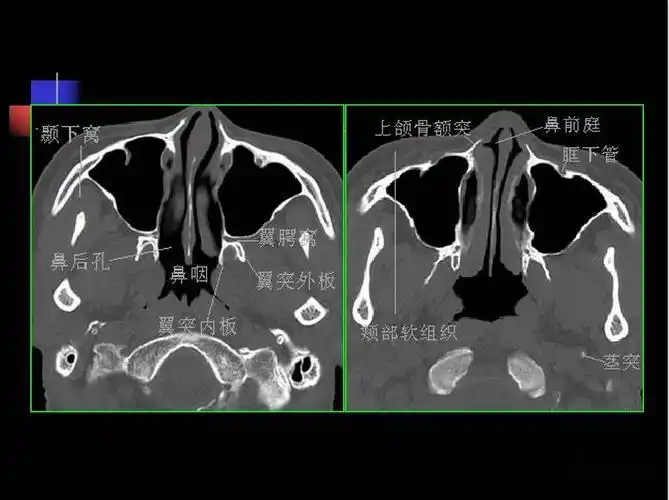

收藏必备鼻咽部的ct详细解剖